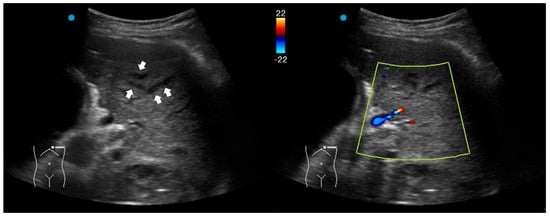

In addition to standardized lateral cephalometric radiographs, comprehensive assessment using dental cone-beam computed tomography (CBCT) and CT has become commonplace in the diagnosis and treatment of jaw deformities. Simulation based on cephalometr...